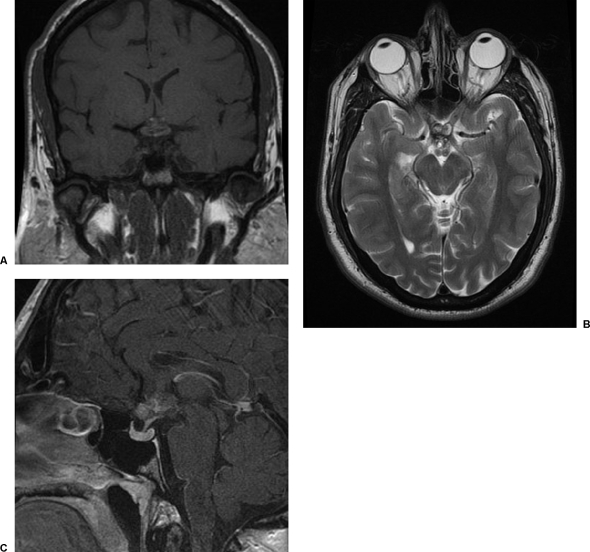

之前的影像學檢查已經(jīng)確定了下丘腦和后視交叉的病變。這已經(jīng)用連續(xù)的核磁共振成像進行了5年的監(jiān)測,較近的一次是在當前報告之前的18個月(圖1).病灶有靜態(tài)表現(xiàn)。病灶在核磁共振成像上返回混合的T1和T2加權(quán)信號。在計算機斷層掃描上沒有顯示鈣化或脂肪密度,隨后的計算機斷層掃描血管造影顯示沒有血管異常。顱咽管瘤被認為是較有可能的放射學診斷。

圖1:A垂體窩的T1加權(quán)矢狀和B,T1加權(quán)矢狀釓后圖像,C大腦的T2加權(quán)軸向圖像。有一個下丘腦/后視交叉損傷,較大軸向尺寸為1.4厘米。它返回不均勻的T2加權(quán)信號,其特征是高強度和周邊和點狀中央低強度區(qū)。T1加權(quán)高信號結(jié)節(jié)區(qū)域顯示釓增強很小。顱咽管瘤被認為是較有可能的,部分血栓形成的動脈瘤,海綿狀血管瘤,出血性神經(jīng)膠質(zhì)瘤和皮樣瘤也被考慮。